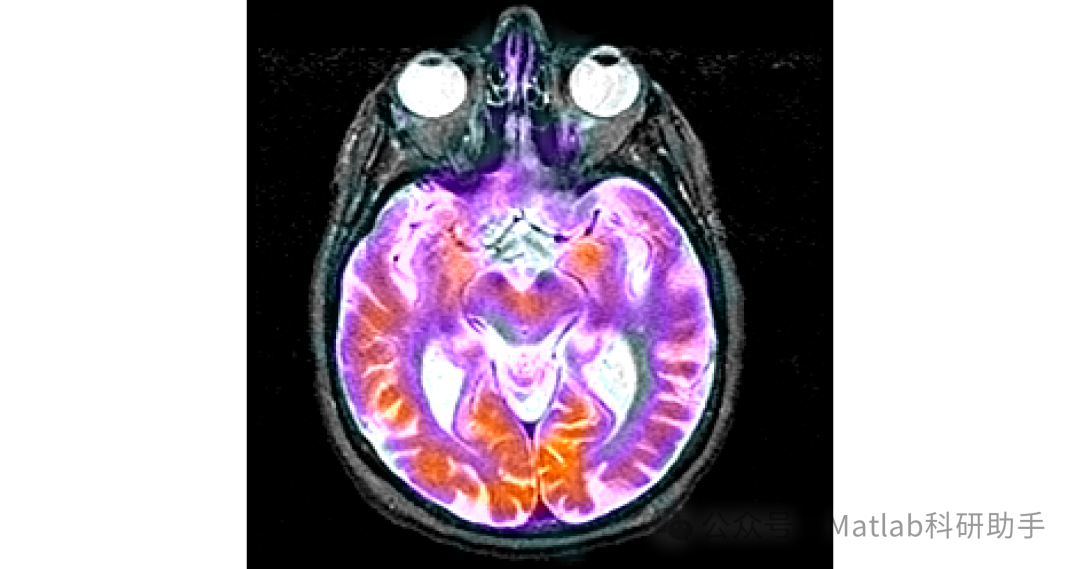

本文针对多模态医学图像融合中存在的细节丢失、边缘模糊等问题,提出了一种基于联合双边滤波和局部梯度能量的多模态医学图像融合方法。通过对源图像进行联合双边滤波预处理,有效地去除了图像噪声,保留了图像的边缘和细节信息;利用局部梯度能量作为融合决策依据,确保了融合图像能够保留更多的细节信息;最后通过直方图均衡化和边缘增强等后处理操作,进一步改善了融合图像的质量。

实验结果表明,该方法在主观评价和客观评价方面均优于传统的图像融合方法,能够生成高质量的多模态医学图像融合结果,为医生的诊断和治疗提供了更有力的支持。

⛳️ 运行结果